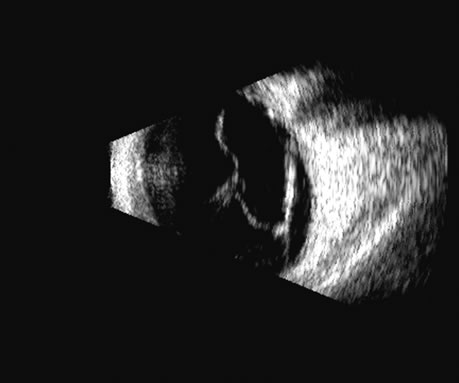

Two-dimensional scans through complex three-dimensional structures, such as preretinal membranes and proliferative membranes, can be confusing unless mapped with three-dimensional conceptualization techniques. Bronson and colleagues15 have emphasized three-dimensional thinking. Although new digital three-dimensional ultrasound systems allow direct volume visualization, it remains useful to understand the technique of conceptualizing three-dimensional structures from individual sections.16 Preretinal membranes (Fig. 15), which may resemble traction detachments in thickness and reflectivity, can often be identified by turning the scan plane of the B-scanner at right angles: the disciform retinal elevation is still seen while the linear nature of a traction sheet is revealed.17 A three-dimensional rendering of a retinal detachment can directly show the conformation of three-dimensional structures (Fig. 16), and images of individual planes can be perceived.

Fig. 16. 3D depiction of a retinal detachment can be helpful in situations in which there is ambiguity among retina, choroid, and schisis. The 3D rotatable display can be perceived from different perspectives, often aiding in the certainty of diagnosis.